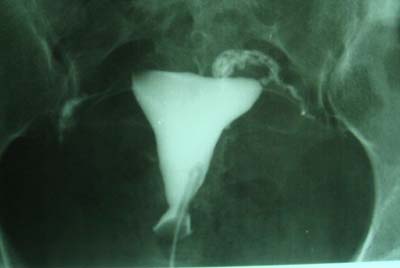

以下是引用haha215315在2008-11-24 8:59:00的发言:[br]放射科的诊断放在输卵管是否通畅、子宫有无病变?其他的不用管了,由妇科医生去掌握。

以下是引用laolang在2008-11-24 10:14:00的发言:[br]放射科的诊断放在输卵管是否通畅、子宫有无病变?其他的不用管了,由妇科医生去掌握 [br] [br] 同意